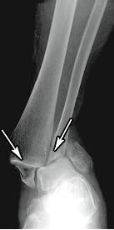

comminuted fracture